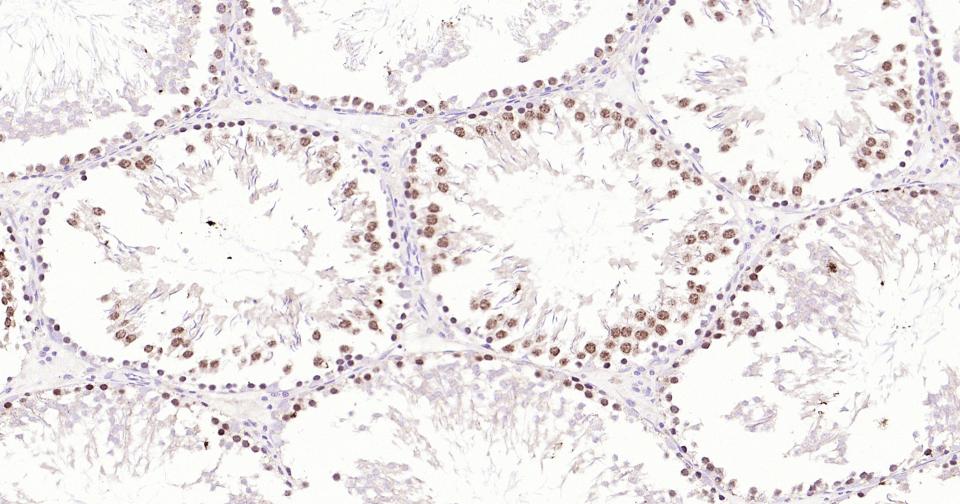

Paraformaldehyde-fixed, paraffin embedded Rat Testicles; Antigen retrieval by boiling in sodium citrate buffer (pH6.0) for 15 min; Antibody incubation with TOP2A Monoclonal Antibody, Unconjugated(bsm-61077R) at 1:200 overnight at 4°C, followed by conjugation to the SP Kit (Rabbit, SP-0023) and DAB (C-0010) staining.